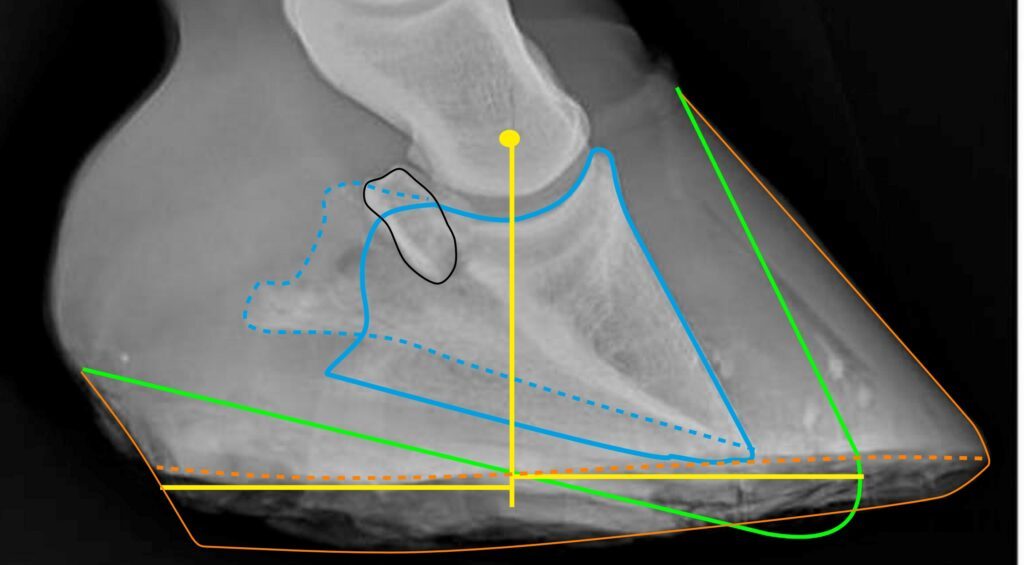

- Orange line = close side of hoof capsule. If it is dark at the bottom of the heel, it means that the hoof wall is too porous to show up on the radiograph.

- Orange dotted line = far side of the hoof capsule.

- Gren line = The hoof shape we want. Now the heels are too high and the toe too long.

- Blue line = close side of the coffin bone

- Blue dotted line = far side of the coffin bone

- Yellow dot = the point from where the horse’s weight loads the coffin bone

- Yellow lines show how the weight is distributed in the hoof. 50% of the weight goes to each side of the vertical line. This means that the heels are overloaded, since 50% of the weight is concentrated on a smaller surface area, which leads to higher pressure per unit area.

The reason the blue lines are different is that the X-ray was taken from too far back and too high.

The bone marked in black is the navicular bone.

This hoof suffers from what they call “Coffin Bone Rotation,” which only means that the hoof wall is no longer parallel with the coffin bone. This is easy to rehabilitate, but NOT the worst problem for this hoof. More complicated to rehabilitate is the fact that the hoof care provider has trimmed away too much under the tip of the coffin bone. This is complicated to rehabilitate, and not all hoof care providers will manage this.